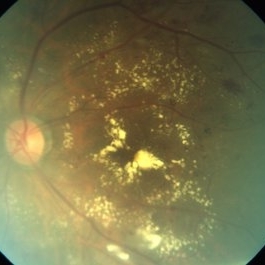

Myopic Degeneration

Sep 10 2014 by Mehul A Shah

Chorio retinal atrophy.

Photographer: Drashti Netralaya

Imaging device: Zeiss FF450

Condition/keywords: myopia